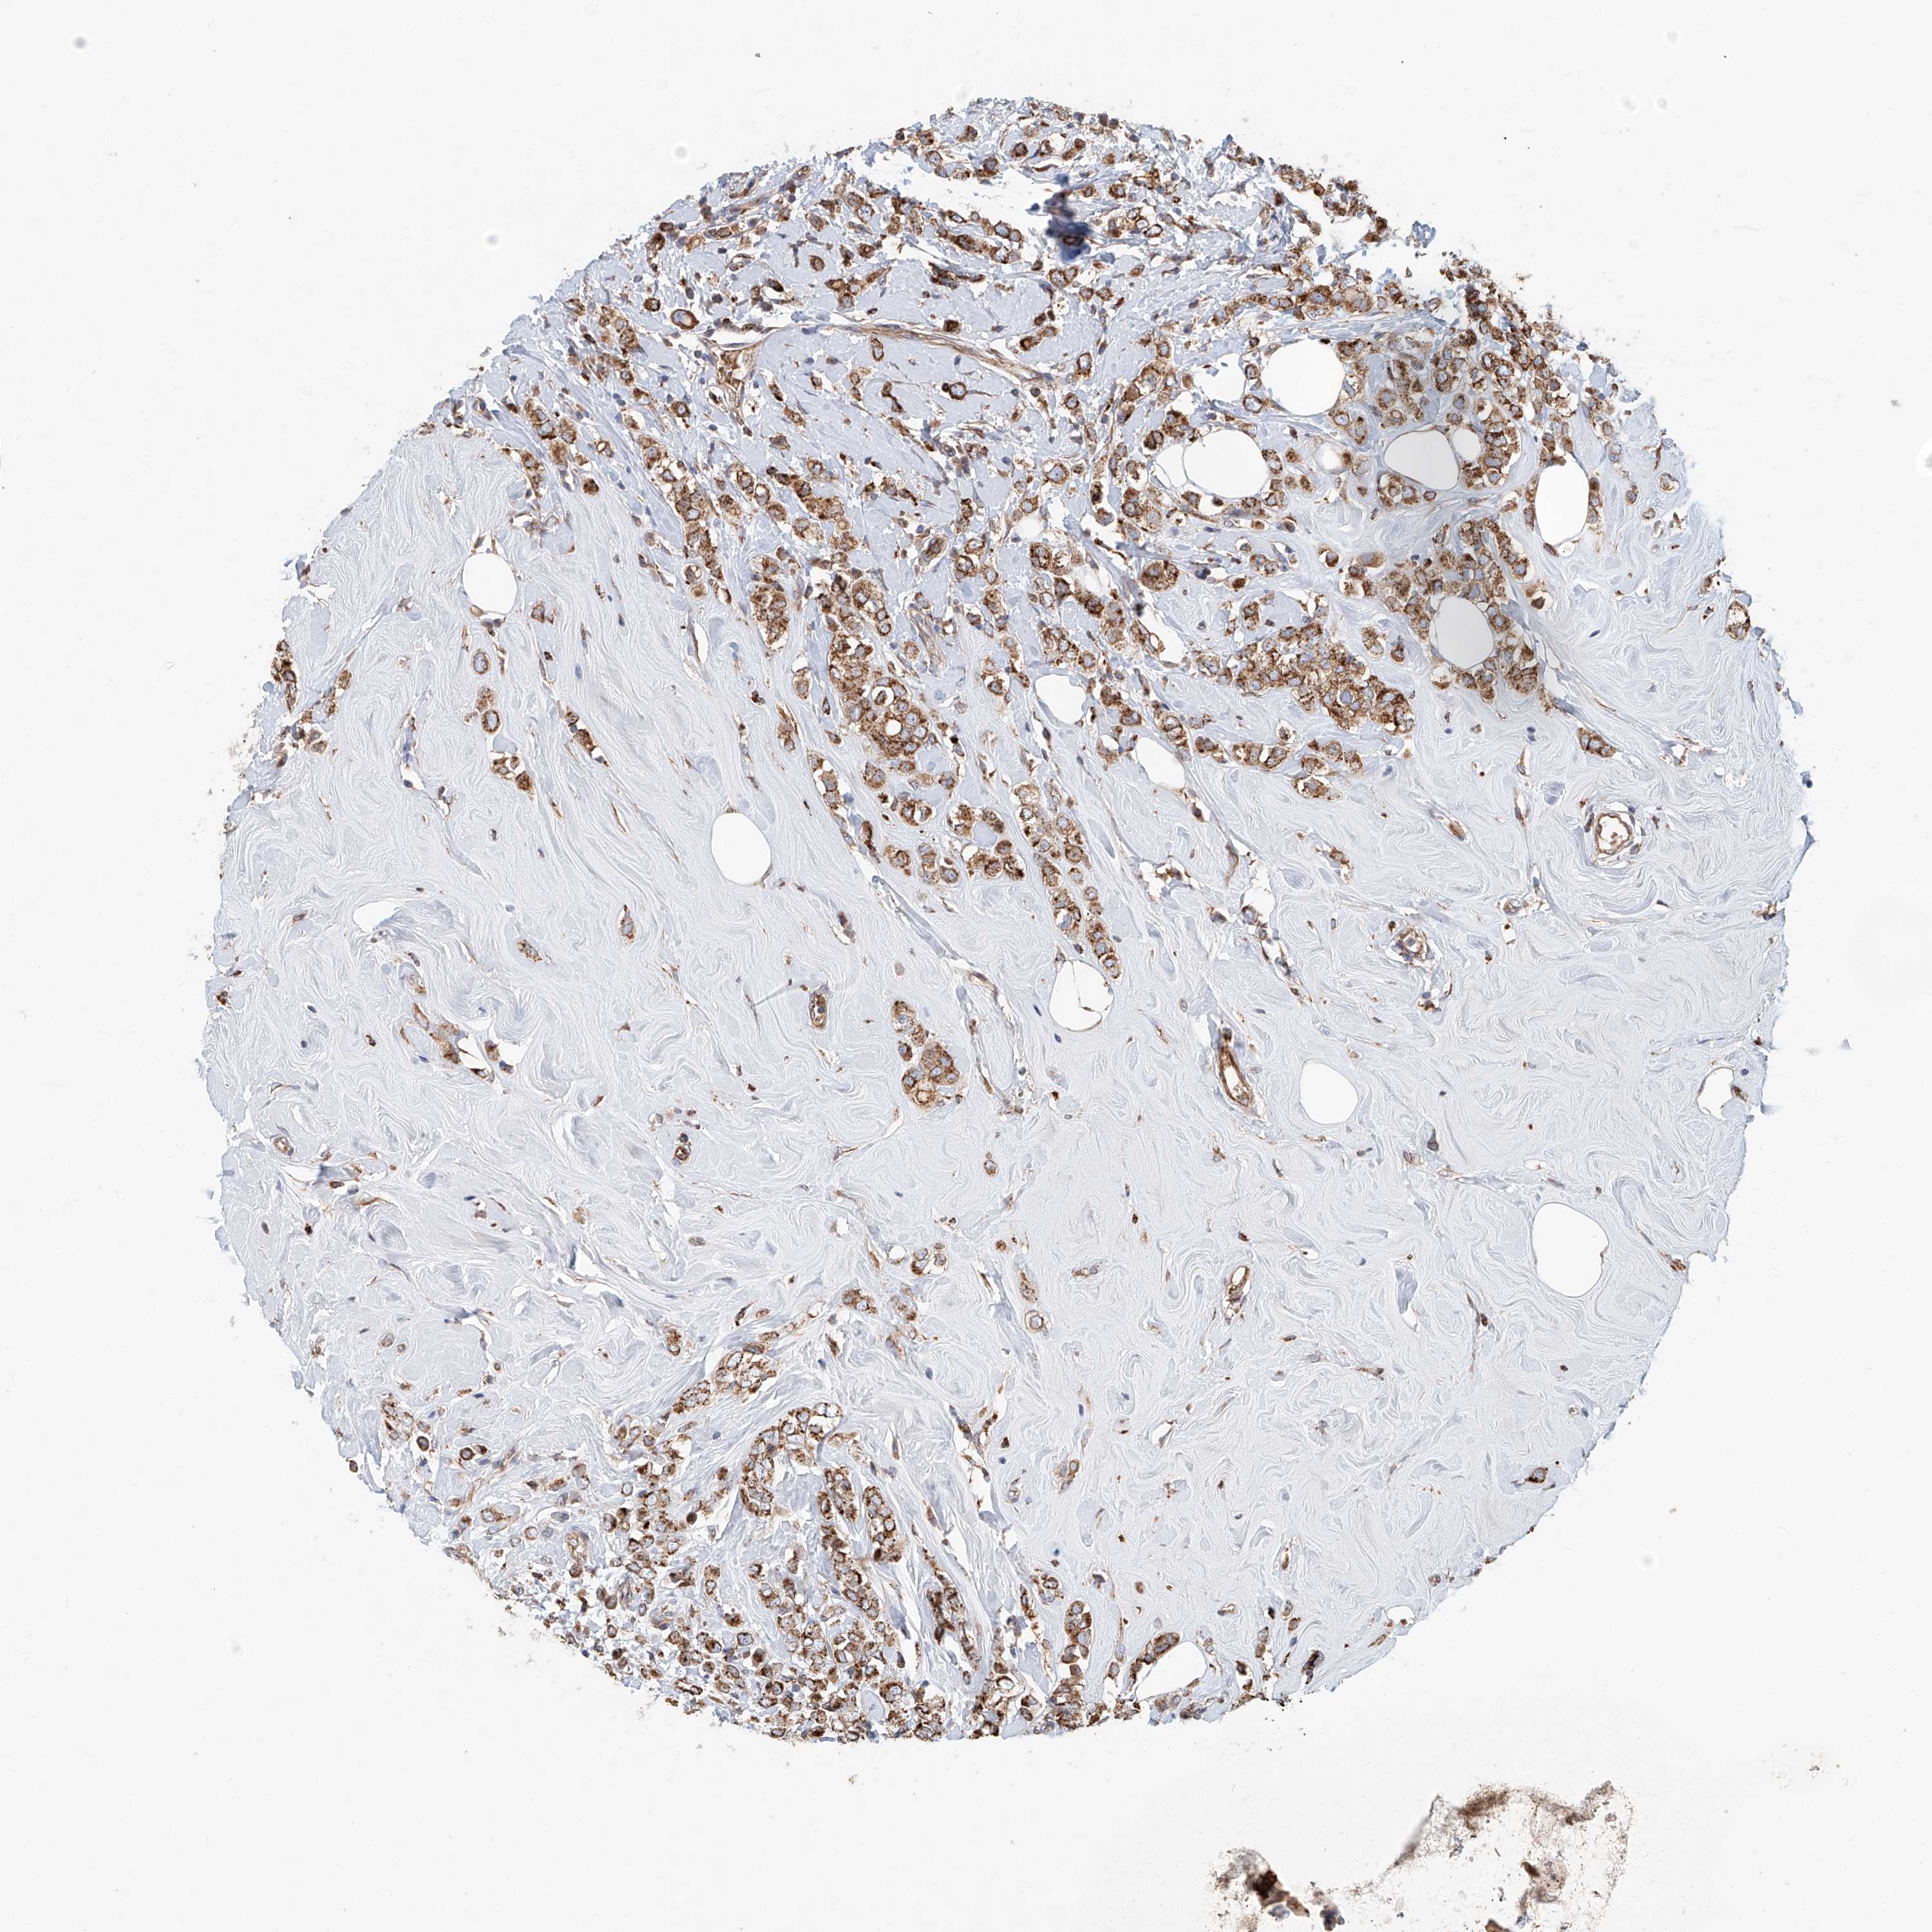

CANCER BREAST CANCER Show tissue menu

BRCA TCGA BRCA VALIDATION PROTEIN EXPRESSION

Breast cancer

Human cancer